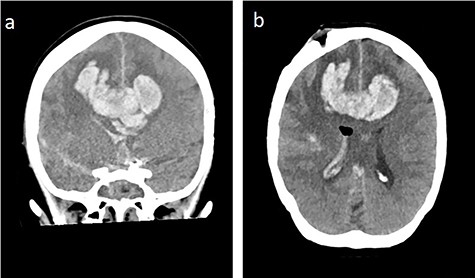

Bifrontal intracerebral bleeding with brain swelling and herniation: (a) coronal cCT, (b) axial cCT

During the next days, the clinical status was stable. On the 43th post-operative day, the clinical situation worsened by an epileptic state with development of maximally dilated pupils without light reaction. CT revealed a massive bifrontal bleeding with rupture into the ventricles and brain herniation (Fig. 7). On the 44th post-operative day, brain death was diagnosed.